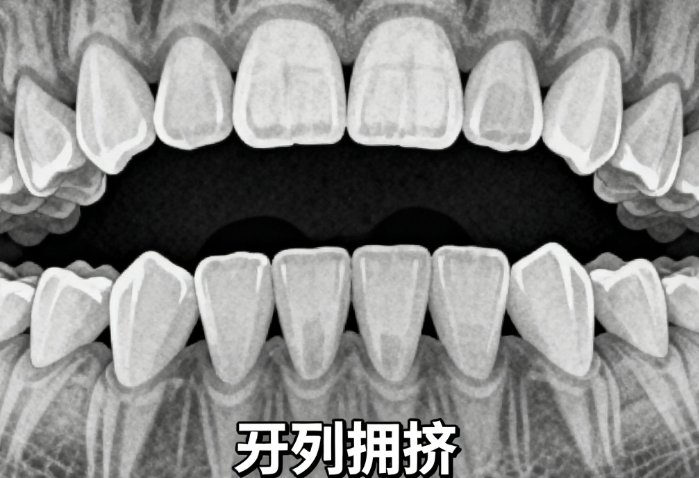

20歲大學(xué)生小林(化名)在段嬌紅醫(yī)生處完成了一年半的正畸治療,原本不敢露齒笑的她,現(xiàn)在笑容自信燦爛。小林初診時存在牙齒中線不齊、門牙縫隙大、功能性下頜偏斜等問題,經(jīng)過詳細(xì)檢查,段醫(yī)生為她設(shè)計(jì)了“妙弓”(MEAW)技術(shù)矯治方案,通過穩(wěn)準(zhǔn)的L形弓絲彎曲,在不手術(shù)的情況下成功糾正了咬合關(guān)系。